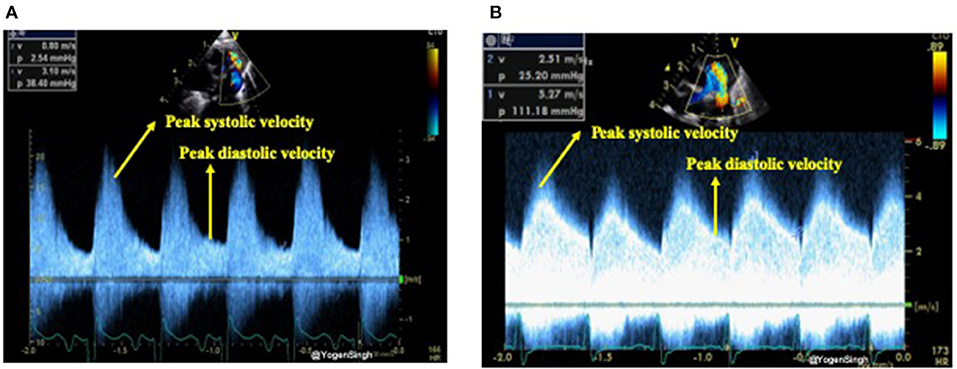

The shunt velocity across the PDA during the cardiac cycle can be obtained by applying pulse or continuous wave Doppler in the ductus arteriosus. The maximum velocity during systole and diastole can be measured. Non-restrictive shunts have a low peak systolic velocity with a high systolic to end-diastolic velocity gradient while restrictive shunts have a high peak systolic velocity and a low systolic to diastolic velocity gradient. If the ratio between peak systolic and end-diastolic velocity is >2 then it is considered as a pulsatile flow pattern while a ratio of <2 is described as restrictive shunt suggestive of a closing PDA (22, 23) (Figure 5).

Figure 5. Assessment of restrictive and non-restrictive (pulsatile) flow pattern on Doppler assessment of PDA. (A) Showing non-restrictive (pulsatile) flow pattern with end-diastolic velocity (EDV) less than half of the peak systolic velocity; and (B) showing restrictive flow pattern with end-diastolic velocity (EDV) more than half of the peak systolic velocity.